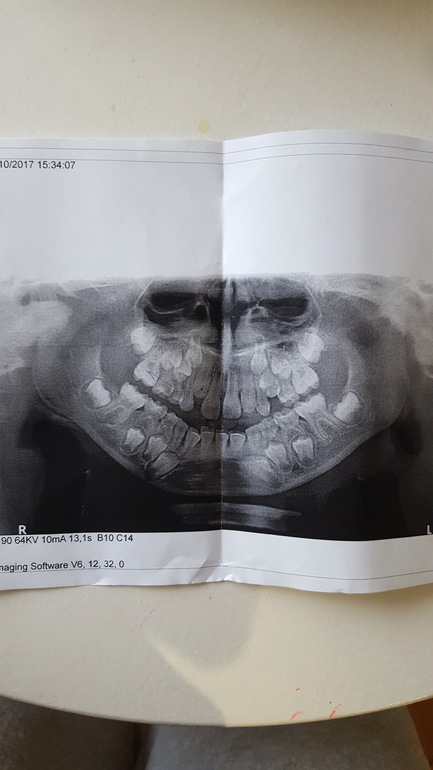

Сделали панорамный снимок. Ортодонт советует установить пластинки на верхнюю челюсть с двумя винтами и с одним на нижнюю. Говорит клыкам нет места. Так ли это необходимо? И если необходимо то как скоро их надо установить? Предлагают записать в очередь, но ждать 8 месяцев, а то и больше. Хотелось бы еще мнения узнать по нашему случаю. Спасибо заранее!

Важно видеть, что во рту. И тогда снимок добавит ясности.